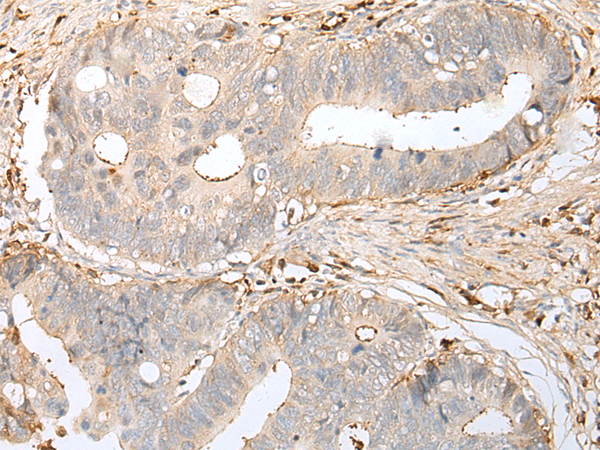

ELISA, IHC |

IHC positive control: |

Human cervical cancer and human gastric cancer |

IHC Recommend dilution: |

25-100 |